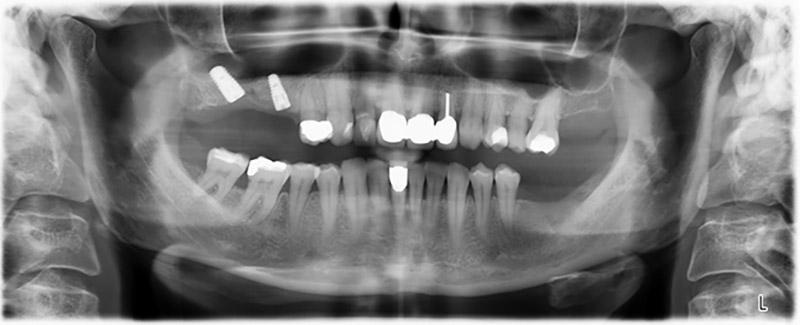

About six months after teeth 16 and 14 were extracted, a digital volume tomography (DVT, Planmeca) examination was performed for planning and risk minimization purposes. It clearly showed that the bone had not regenerated to the desired volume (Fig. 2 to 7).